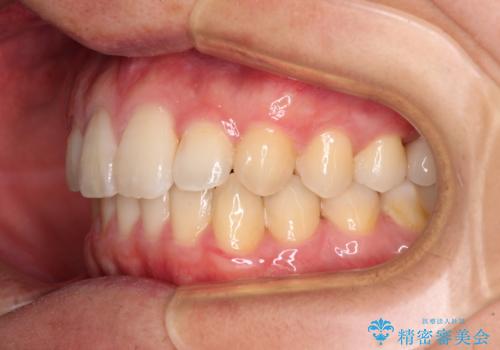

前歯のクロスバイトと抜歯が必要な奥歯の虫歯 インビザラインとインプラント治療

- 前歯のクロスバイトと、大学生のころから放置している虫歯を気にして来院された患者様です。

マウスピースでの矯正治療を希望されていましたが、前歯のクロスバイトは不十分な仕上がりや歯髄壊死などのリスクが高くなるため、術前にワイヤーで大まかに整えてからインビザラインにて矯正治療を行うこととしました。

奥歯の虫歯は抜歯が必要であったので、矯正治療前に抜歯をし、矯正治療と並行してインプラントによる補綴治療を行うこととしました。